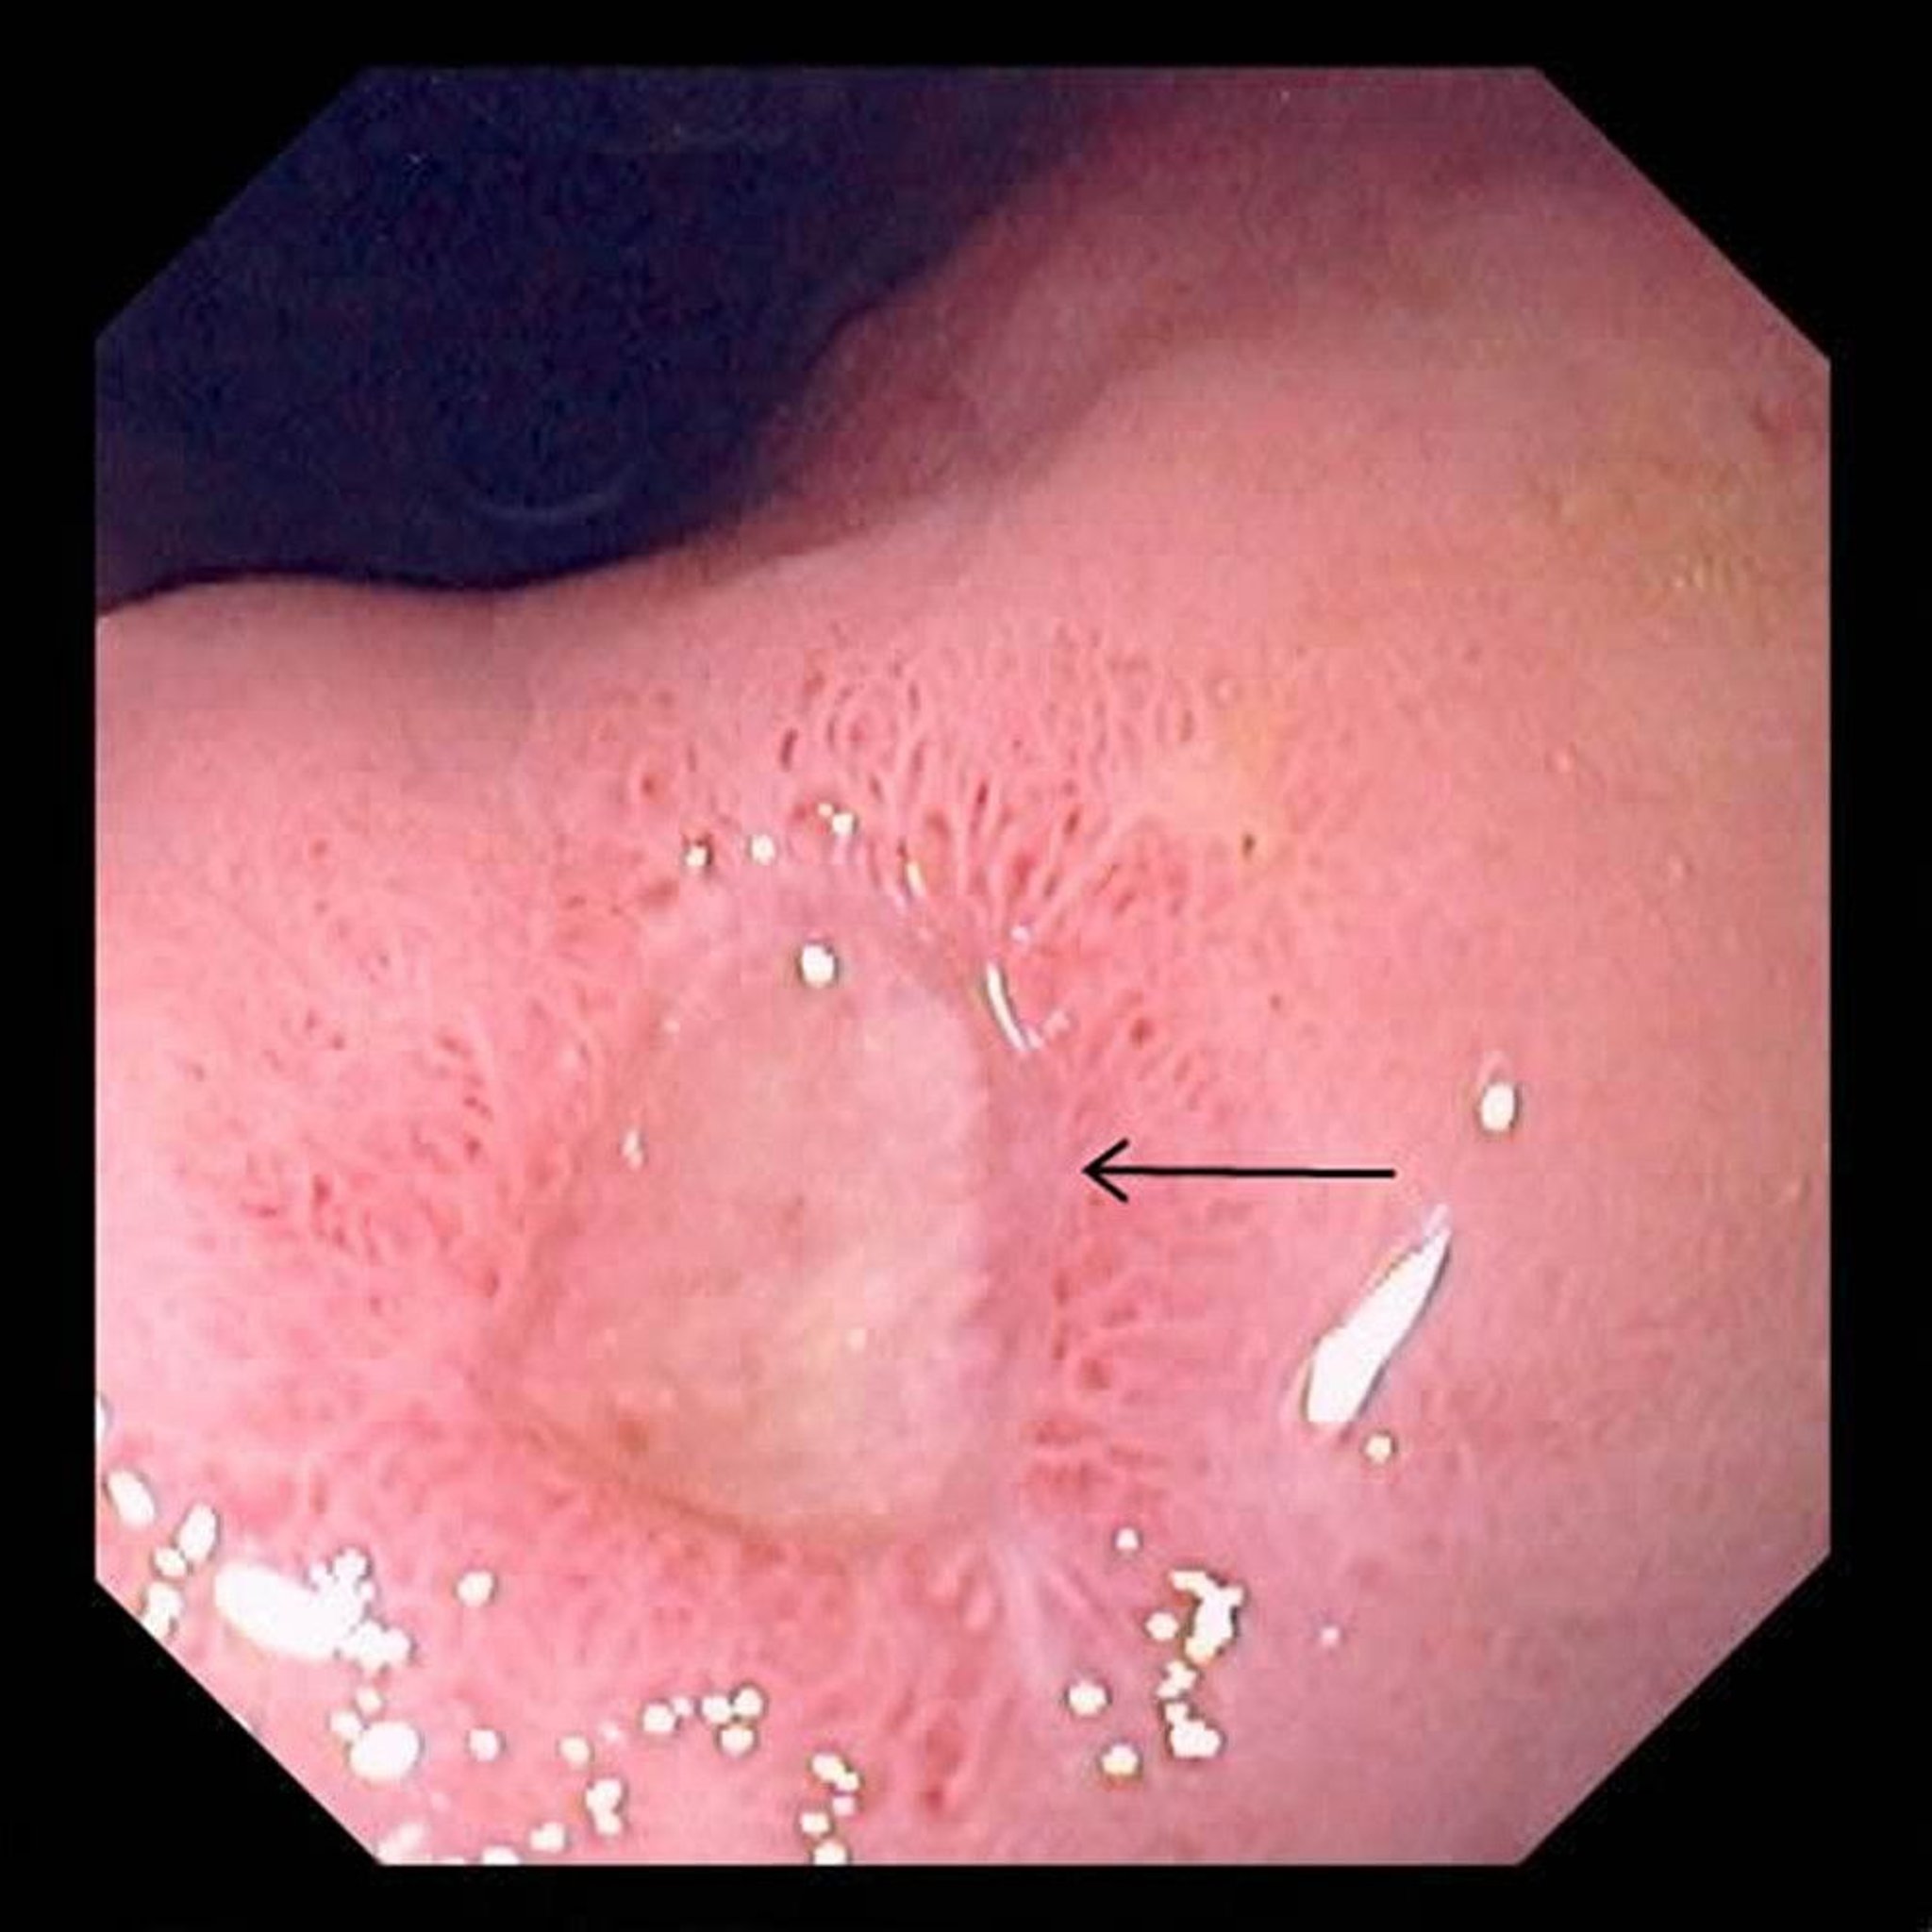

Gastric Ulcer

This photo shows a large ulcer (arrow) in the stomach.

Photo provided by David M. Martin, MD.